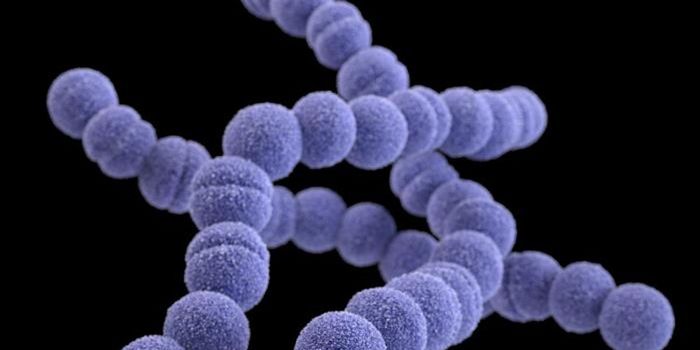

JUL 12, 2021MicrobiologyBacterial pathogens are thought to be a growing threat to public health. Streptococcus pneumoniae, for example, is most ...